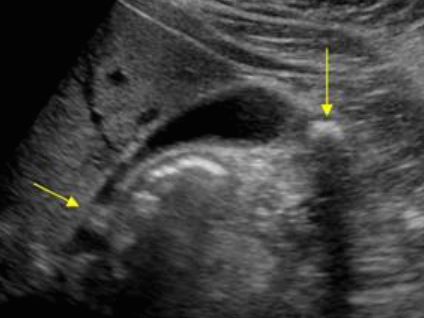

- 강한 고에코의 반사체 (strong echogenic sign)

- 후방음향음영 (posterior acoustic shadow)

- 환자 체위에 따라 움직임 (rolling stone sign)

- Wall-echo-shadow (WES) triad = double arc shadow sign

- 콜레스테롤 결석은 강하고 선명한 후방음영이 존재한다